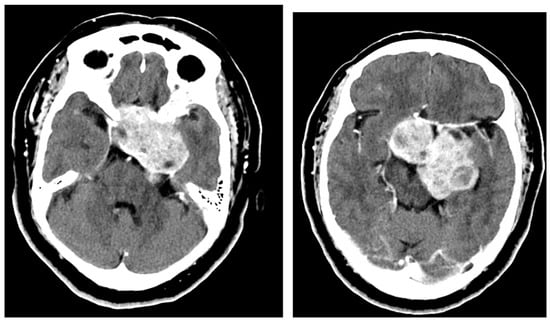

A 74-year-old male presented with cognitive decline over several months, as well as memory and visual deficits, accompanied by a significant decline in balance. Imaging revealed a large extra-axial mass, measuring 4.3 × 6.3 cm, located at the right anterior clinoid process. The mass showed significant suprasellar and cavernous sinus extensions into the bilateral anterior fossa, middle fossa, and partially within the posterior fossa in retroclinoid space, overall resulting in significant compression of the optic chiasm apparatus and brainstem. There was significant vasogenic edema and obstructive hydrocephalus. This is illustrated in Figure 7.

Figure 7.

Preoperative axial (left) and coronal (right) MRI with contrast demonstrating a large, heterogeneously enhancing mass centered on the right anterior clinoid with cavernous sinus, suprasellar, middle fossa, anterior fossa, and intraventricular extension. It measures approximately 4.3 × 6.3 cm.